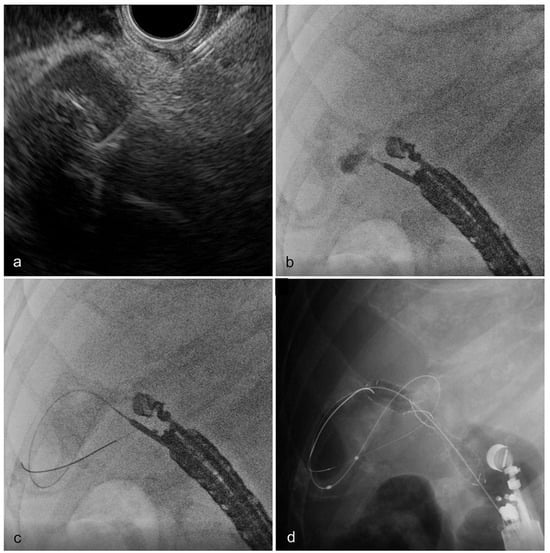

2.4. EUS-GBD Technique